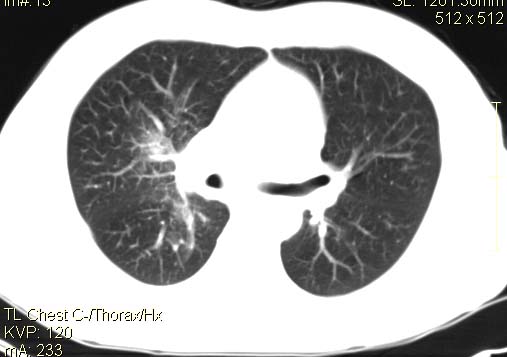

以下是引用qingyuan在2007-4-17 14:19:00的发言:[br]右肺下叶外侧后段胸膜下区节结样病变、分叶、内可见空洞,壁厚薄不均,胸膜凹陷、肺门周围区纹理增粗、僵硬、并近似小结节样改变,肺门区软组织节结、纵膈淋巴结肿大,患者病史长、抗炎治疗无好转炎性改变基本排除,考虑:右肺下叶周围型肺癌伴纵膈及右肺门区淋巴结转移、肺内淋巴管受侵。